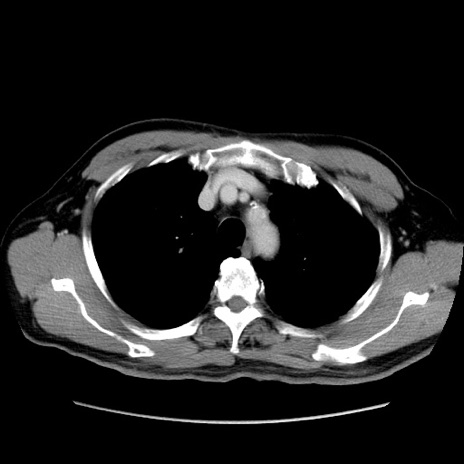

症例34(横断像)

【症例】60歳代 男性

【主訴】右鼠径部膨隆

【現病歴】1年程前より右鼠径部膨隆あり。自己にて還納可能だったため放置していた。3時間前より右鼠径部の脱出を認め、還納困難となり受診。

【身体所見】右鼠径部に小児頭大の膨隆あり。弾性硬であり、用手還納は困難。左鼠径部にも膨隆を認める。脱出はなし。